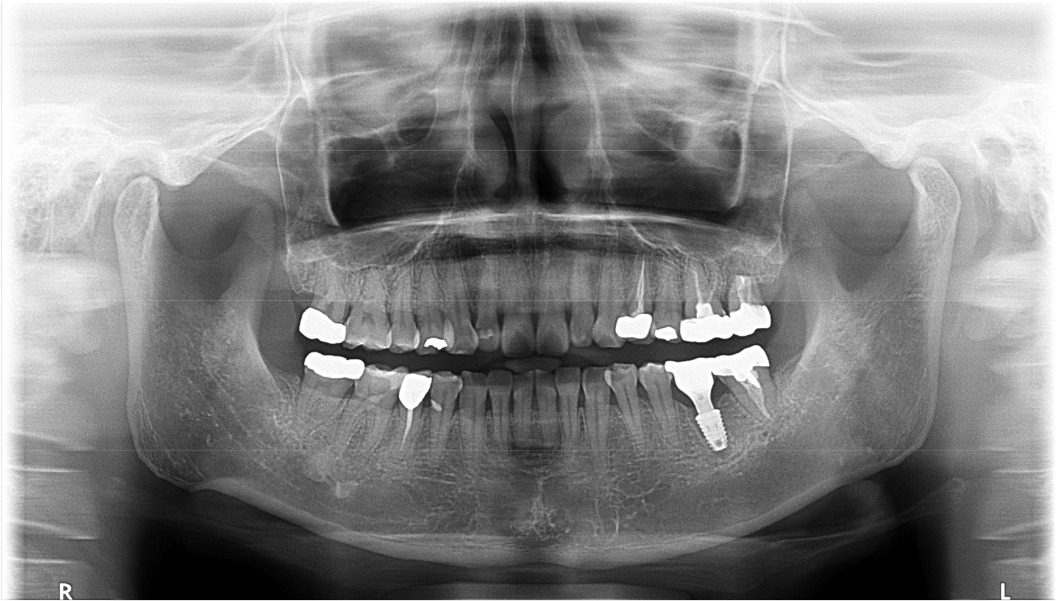

A 43-year-old female needing implant treatment and extraction of the upper left molar visited the clinic. Her upper left second molar showed second degree of tooth mobility and had a treated history of intentional replantation (Table 1). The apical lesion of this tooth disappeared after the intentional replantation (Fig. 1A, 1B). There are no signs of additional infection or periodontitis-related inflammation (Fig. 2). The alveolar bone height of this site was more than 5 mm, which facilitates the treatment plan to conduct the immediate implant placement with elevation of the maxillary sinus membrane using hydraulic pressure.

Under local anesthesia with 2% lidocaine (1:100,000 epinephrine; Huons, Seongnam, Korea), the upper left second molar was extracted with minimal damage to the alveolar bone and treated with subgingival curettage to remove apical lesions on periapical radiographs (Fig. 3A, 3B). Consequently, the maxillary sinus membrane was elevated using the hydraulic sinus lift technique through the extraction socket. Before elevation, using the sinus lift kit (CRESTAL APPROACH Sinus KIT; Shinheung, Seoul, Korea), no signs of perforation on the maxillary sinus membrane were verified.